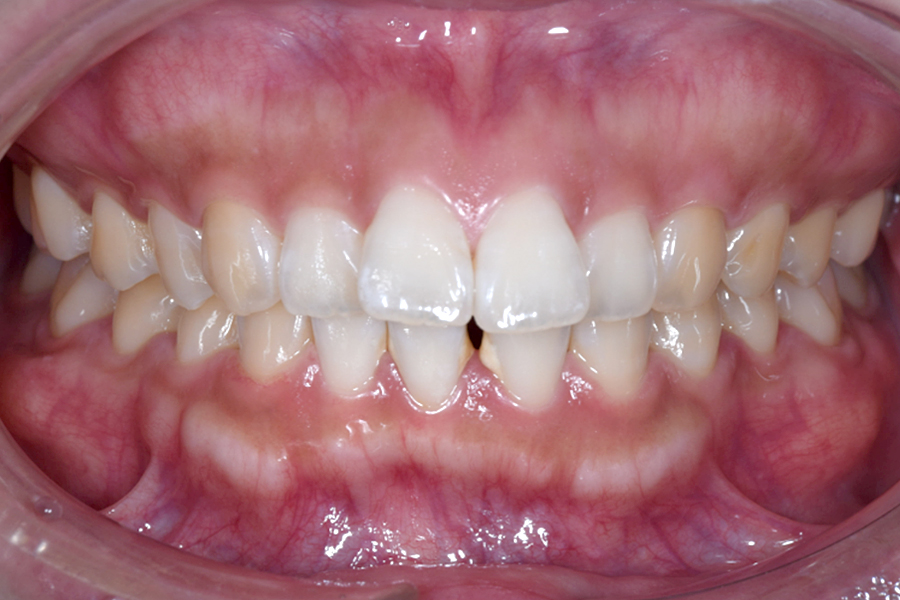

| 主訴 | 歯並びを治したい |

|---|---|

| 治療期間 | 1年9か月 |

| 治療費 | ¥1,023,800(税込) |

| 治療内容 | 目立ちにくいマウスピース矯正(非抜歯矯正) 歯と歯の間に隙間をつくることにより、 歯列弓を広げながら治療を行いました。 |

| 治療のリスク | ・後戻りする可能性があるので リテーナーを最低でも矯正期間以上はつけること ・歯の移動中に、歯の神経が過敏になり冷たいものや熱いものがしみたりする場合があります。 |